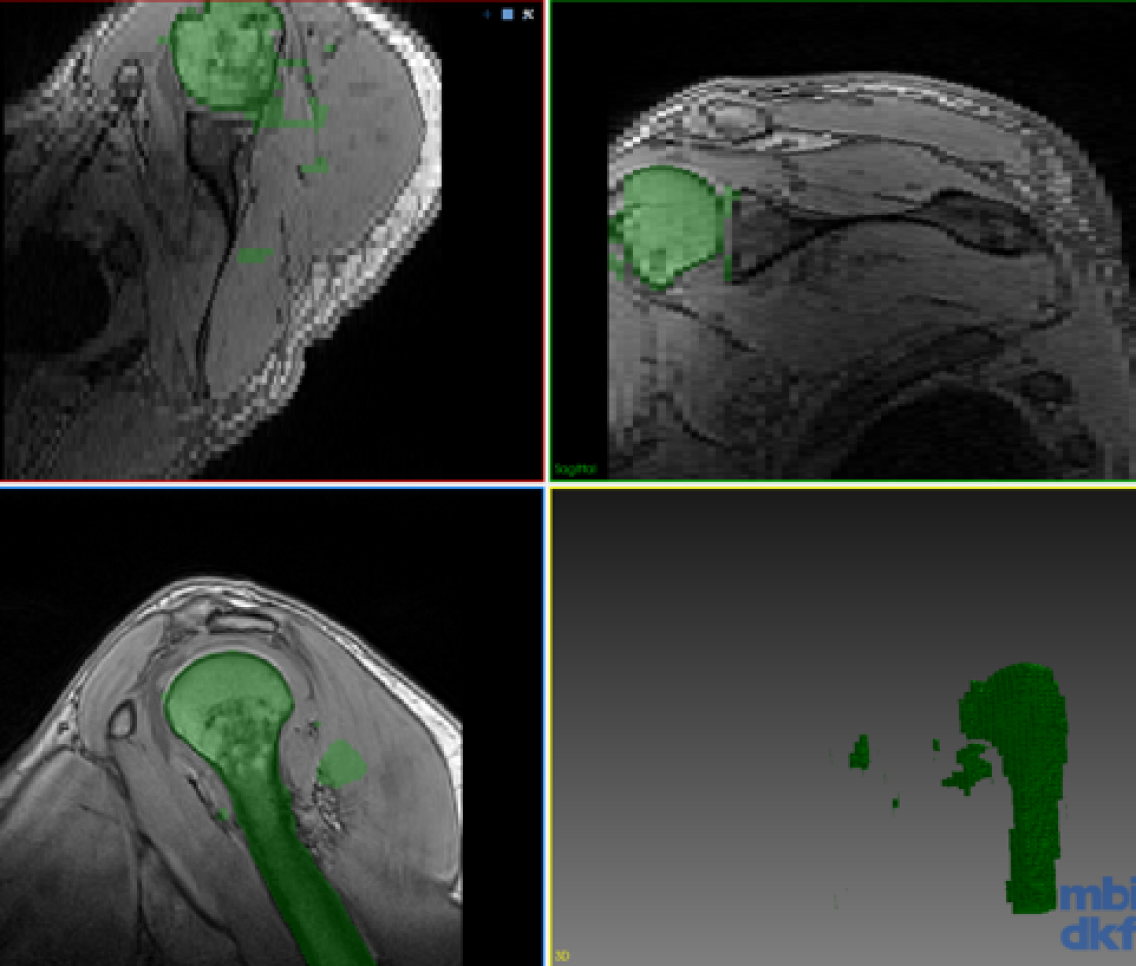

Refer to caption

(a) Gold Standard

Figure 3: Segmentation of the test volume with different methods.

Our experimental dataset consists of 9 Dixon sequences of left shoulder collected with 1.5 Tesla at resolution of 0.91 mm x 0.91 mm x 3 mm, corresponding to 192x192x64 voxel resolution. Humerus and scapula bones were annotated by an expert. Our goal is to combine knowledge from different data for a network that can segment both anatomical structures. We evaluated our proposed method for the three scenarios shown in the table in Fig. 2. One volume each was fixed randomly for validation and testing each of all scenarios. The first scenario (Case 1) tests a typical setting where different anatomies were of interest and thus annotated in separate studies. The second scenario (Case 2) aims to observe advantages of incremental training with minimal effort, i.e., incrementally annotated data, giving insight on an extreme case where a single volume annotation is provided. The last scenario (Case 3) studies the feasibility of combining learned segmentation information from different anatomy and images of different contrast. The methods were implemented with Tensorflow [14] and ran on an Nvidia Titan X GPU. Proposed network is implemented in 2D, hence 646464 image samples per volume given in Fig. 2. For a fair comparison, we fixed all parameters across different models to kcsubscript𝑘𝑐k_{c}==505050, krsubscript𝑘𝑟k_{r}==303030, α𝛼\alpha==0.50.50.5, tMCsubscript𝑡MCt_{\mathrm{MC}}==292929, batch size of 8 images, and trained all models for 1000 epochs. Used network (cf. Fig.1) has a first convolutional layer with 64 filters and the amount of filters double at every coarsening level. Each convolutional layer is proceeded with a batch normalization and ReLU activation. For CoRiSeg, we use a VGG16 network [7] pre-trained on ImageNet [13]. While a VGG trained on a medical image set would be expected to provide more accurate dcontsubscript𝑑contd_{\mathrm{cont}} score, training set of ImageNet is not matchable by any annotated medical database. We used Dice similarity coefficient and average symmetric surface distance for evaluating segmentation performance across tested methods (cf. Table 1). We compared our proposed methods: LwfSeg with its extensions with exemplar sets AeiSeg and CoRiSeg. Upper bound cases are presented with networks trained on only a given anatomy/dataset, i.e., without any incremental learning and hence without the need to preserve “old” (extra) information. We also show results from finetuning for comparison, although catastrophic forgetting is a known problem. In Fig. 3, we showcase qualitative results from different scenarios (cf. table in Fig. 2).